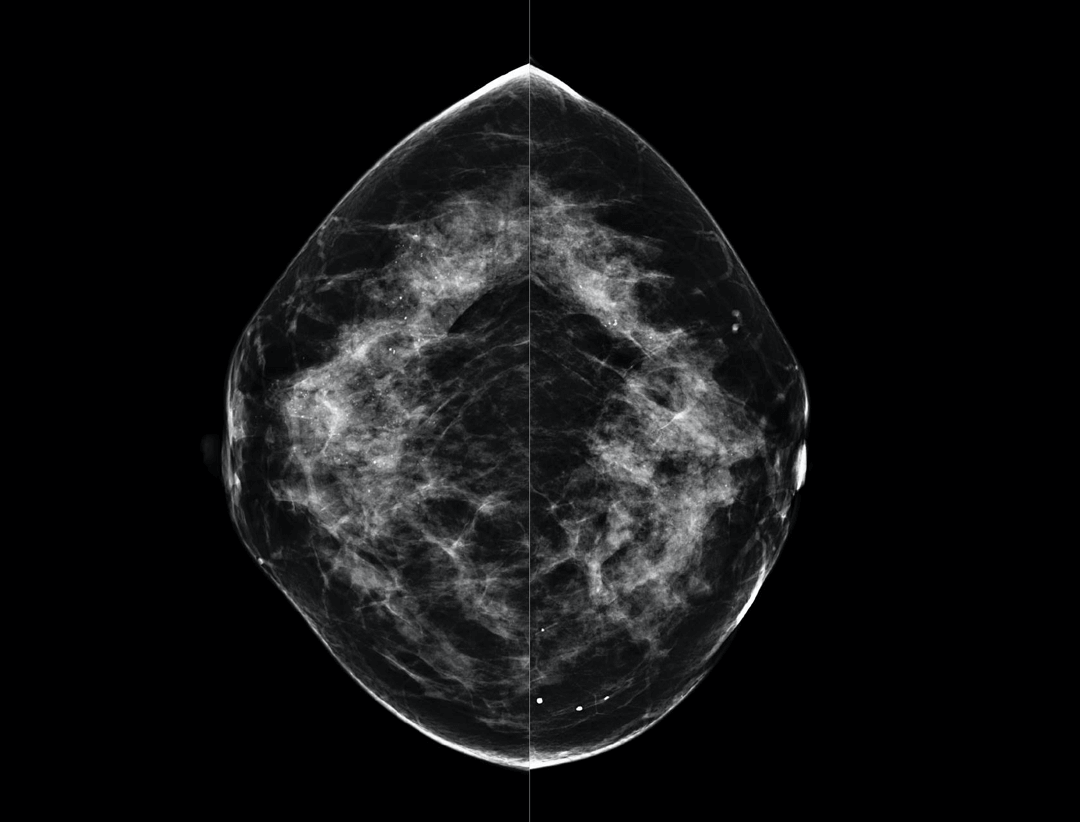

Large coverage amorphous-silicon (a-Si) flat panel detector featuring an optimized active matrix array provides high spatial resolution and high image acquisition speed at a lower dose.

High performance tungsten target X-ray tube offers high resolution image for both dense and fatty breast densities.

Intelligntly detects breast density and thickness, then auto selects the appropriate filter combination.